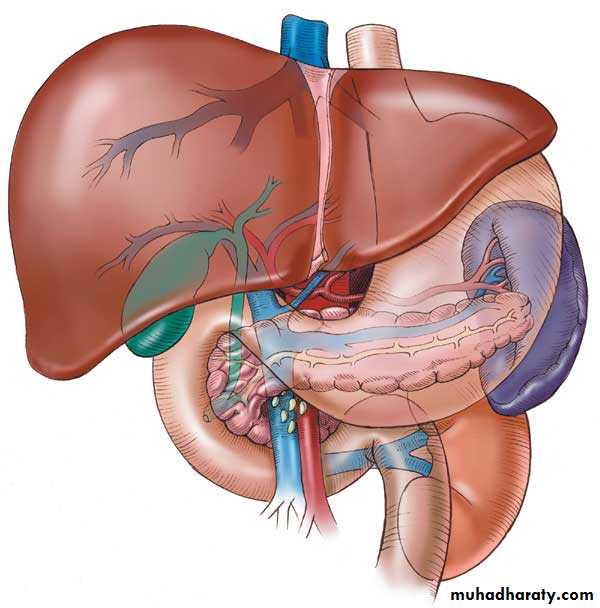

liver

The largest single organ in the human body.In an adult, it weighs about three pounds and is roughly the size of a football.

Located in the upper right-hand part of the abdomen, behind the lower ribs

The liver is divided) into four lobes: the right (the largest lobe), left, quadrate and caudate lobes.

Supplied with blood via the protal vein and hepatic artery.

Blood carried away by the hepatic vein.It is connected to the diaphragm and abdomainal walls by five ligaments.

Gall Bladder

Muscular bag for the storage, concentration, acidification and delivery of bile to small intestine